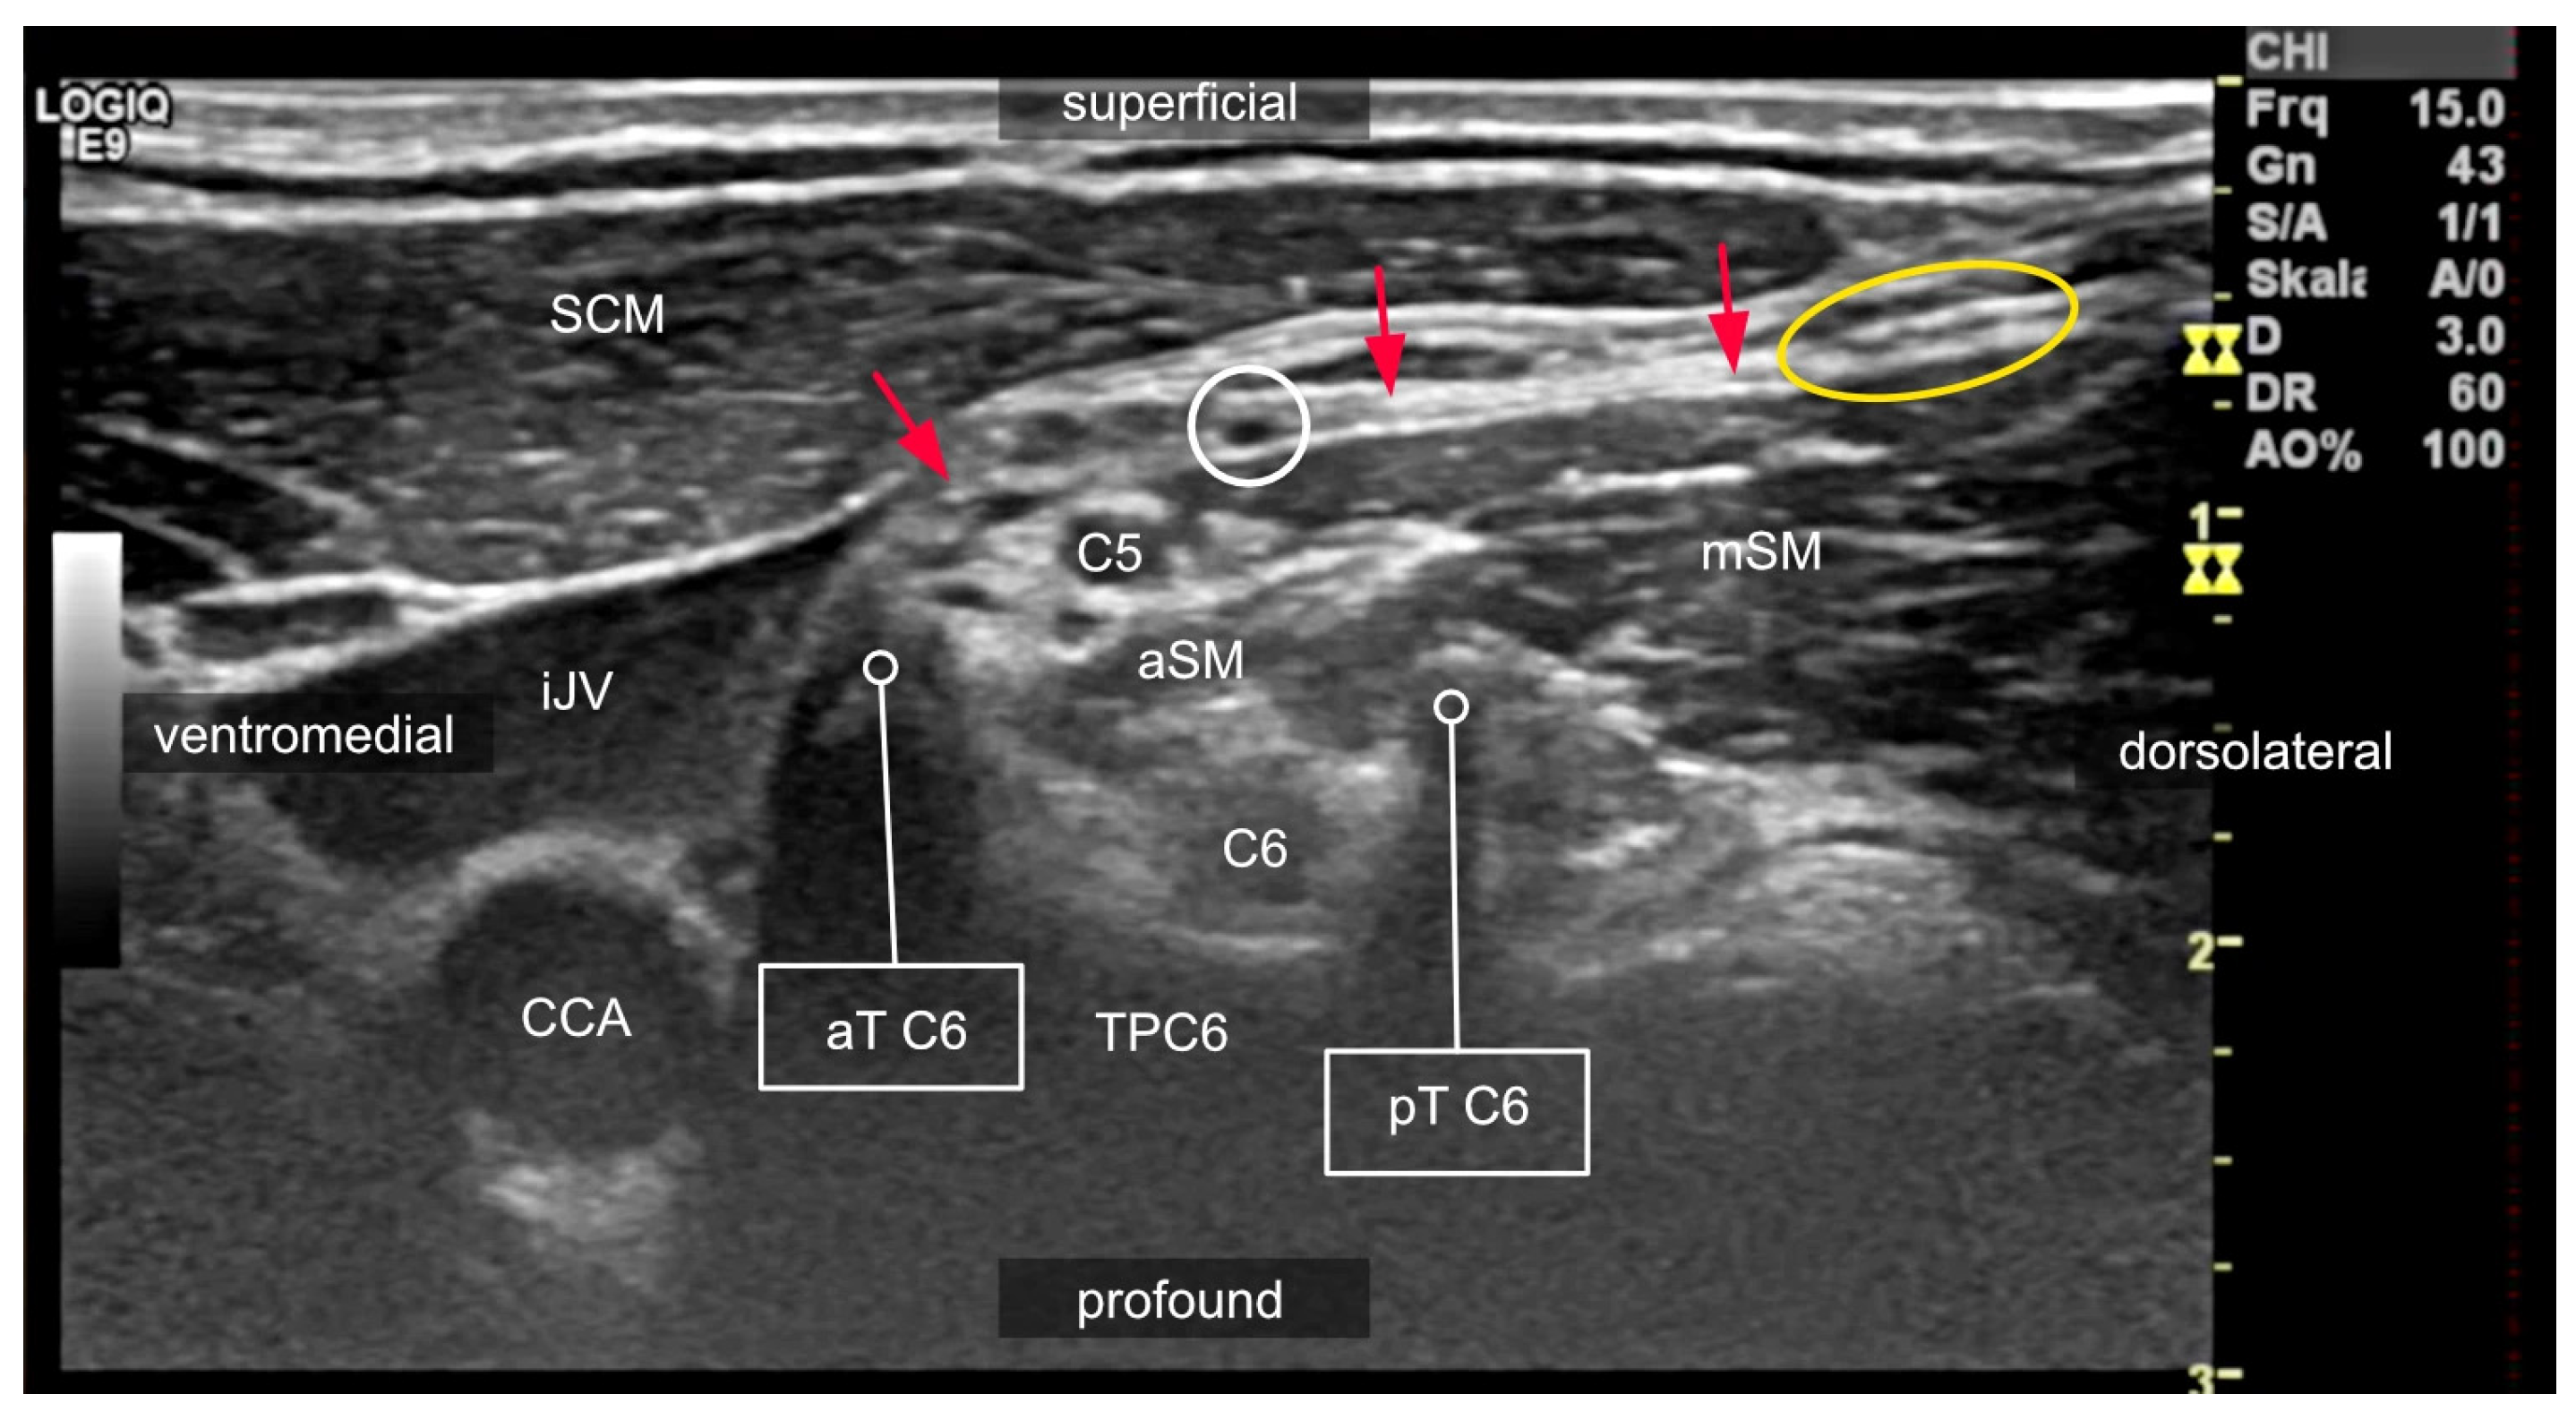

2.2. Anatomical Variations in the Scalene Gap

2.3. Variants of the Course of the Ventral Rami

2.4. Compartments of the Lateral Neck and Their Relevance to Side Effects